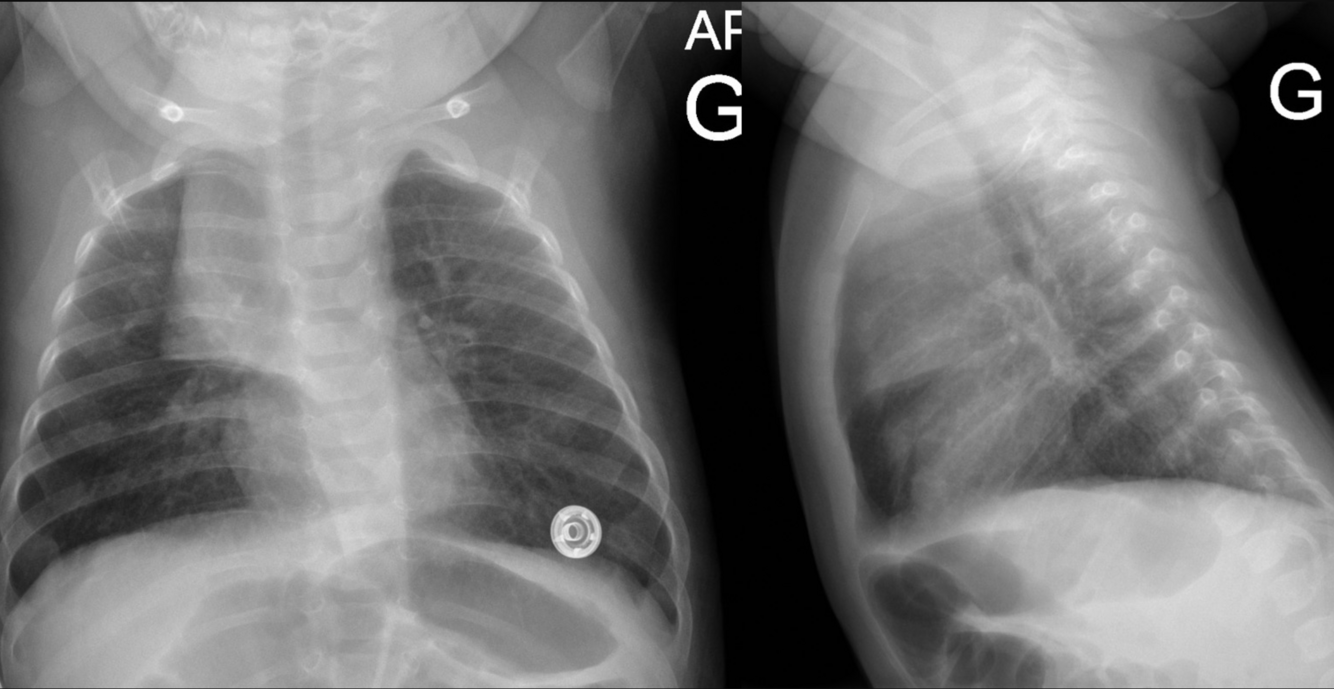

Une mère se présente à la clinique avec son bébé de 5 mois qui fait de la fièvre et tousse depuis 48 heures. À l’examen physique, la température rectale est à 39,5°C avec une FR à 24/min. Il y a une rhinorrhée claire profuse. L’auscultation pulmonaire démontre un murmure vésiculaire symétrique sans crépitants ou sibilances. Il n’y a pas de wheezing.

Quelle est la meilleure interprétation de la radiographie pulmonaire?

Réponse de l’expert: Radiographie pulmonaire normale. Thymus asymétrique, variante de la normale.